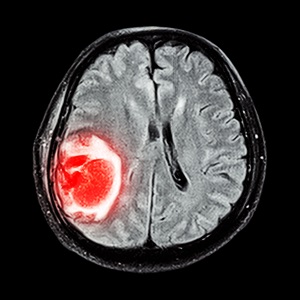

- МРТ или КТ с контрастом